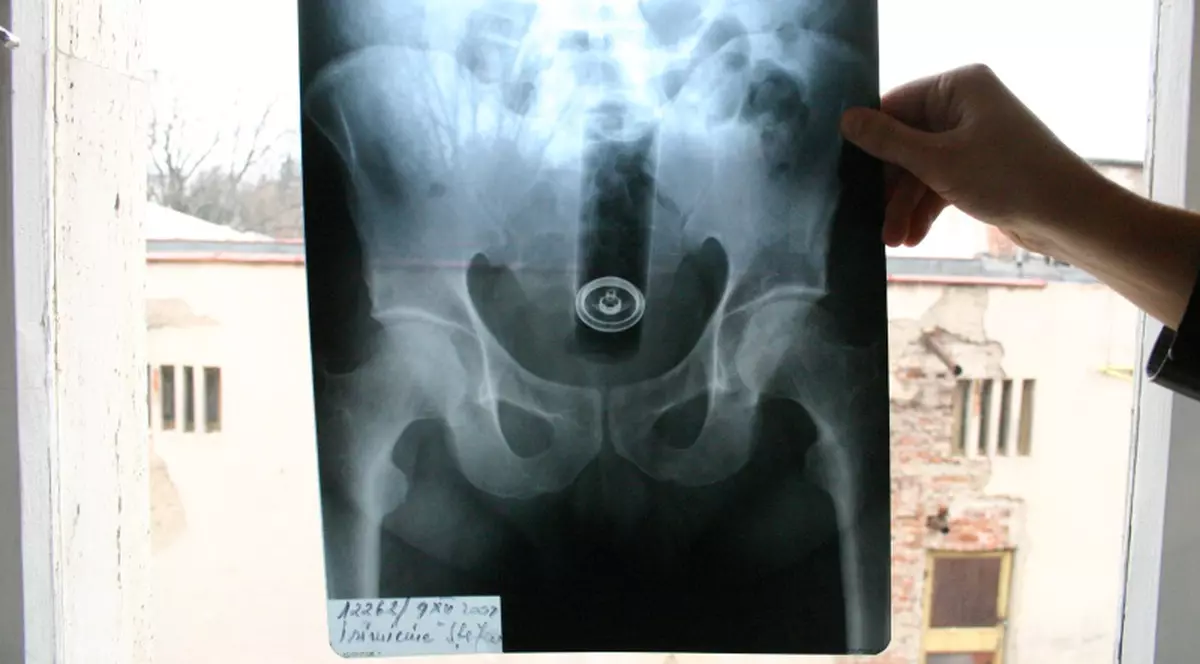

Extrem de ruşinat, bărbatul, deşi cu dureri extreme, a aşteptat până ce nu numai cabinetul, ci şi holul Unităţii de Primire a Urgenţelor s-au eliberat şi a intrat pentru a-şi prezenta „problema” medicilor. „Ne-a spus că stătea aşa încă de pe data de 6, însă nu a avut curaj să vină şi a sperat că problema se va rezolva de la sine. A fost un procedeu destul de uşor şi tubul de spray i-a fost scos cu tot cu capac. I l-am dat acasă drept amintire. A spus că a încercat o experienţă nouă”, a povestit unul din medicii din cadrul UPU Botoşani.

Pacientul a refuzat internarea şi a plecat acasă fericit că poate sta din nou pe scaun.